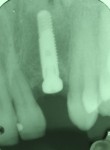

Sinus Lift With Simultaneous Implant

Sinus Lift